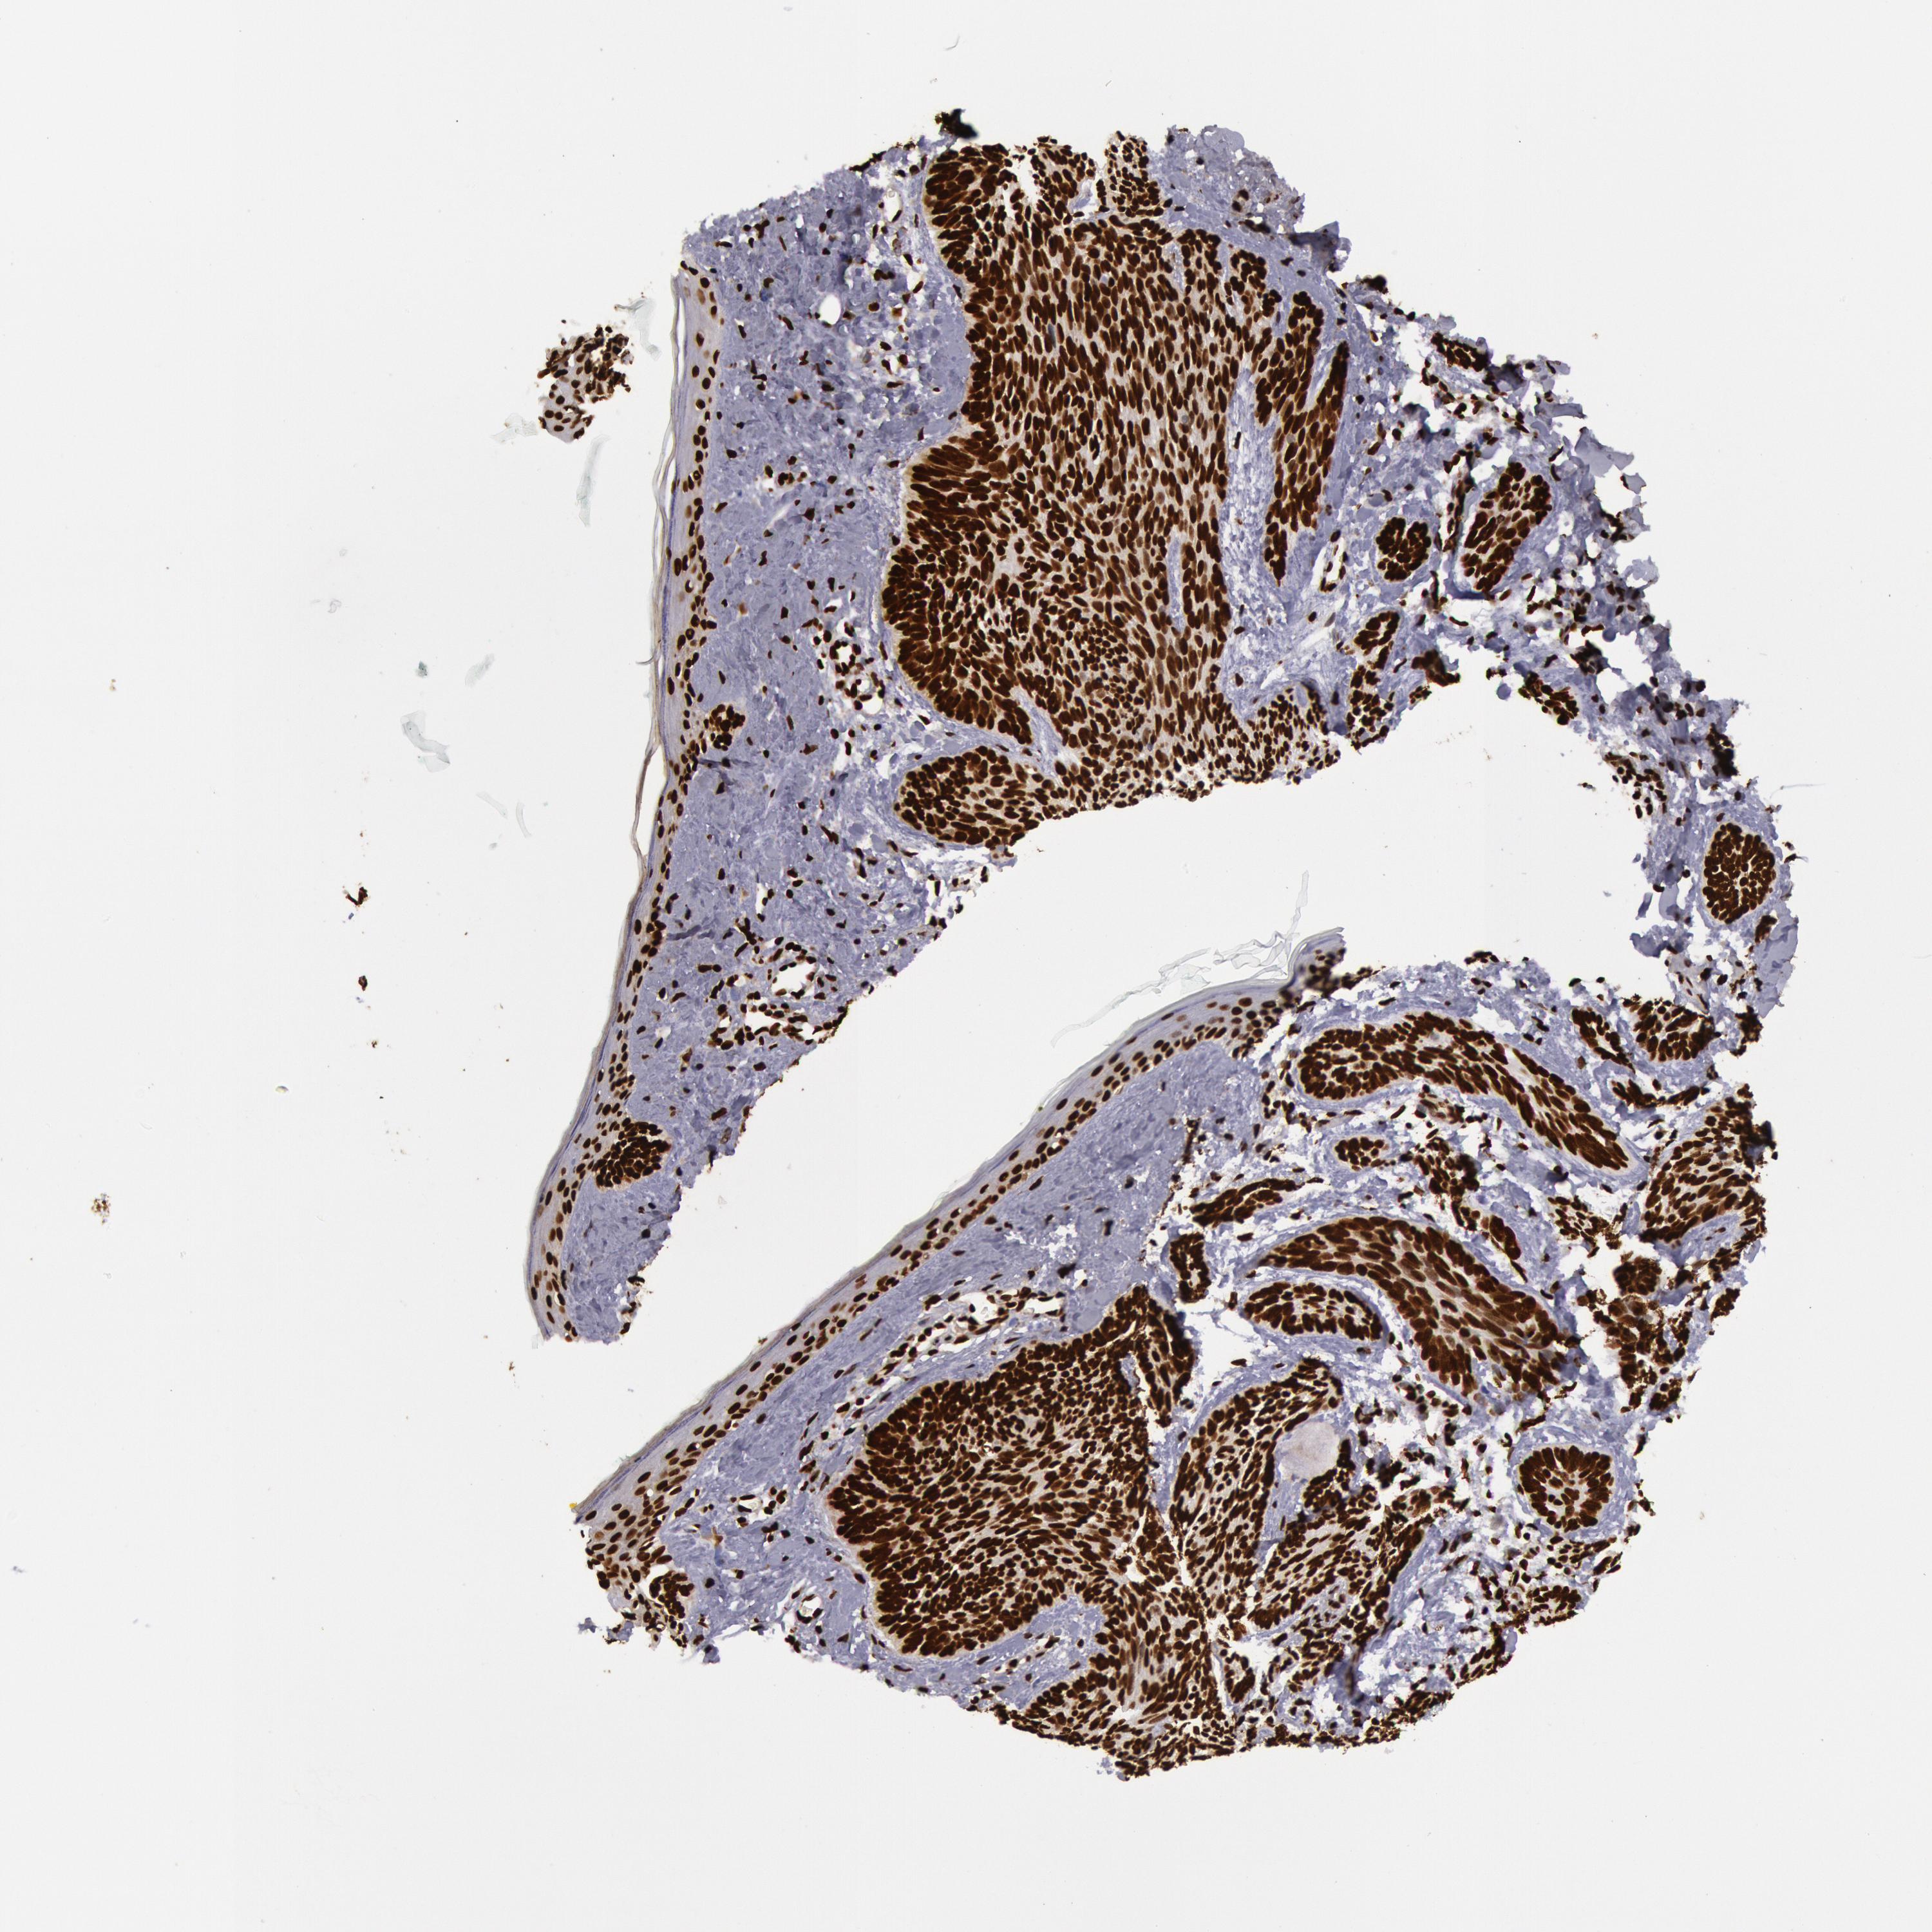

SKIN CANCER - Protein expressioni

A mouse-over function shows sample information and annotation data. Click on an image to view it in a full screen mode. Samples can be filtered based on level of antibody staining by selecting one or several of the following categories: high, medium, low and not detected. The assay and annotation is described here.

Each image is clickable and will lead to virtual microscopy that enables deeper exploration of all samples and also displays staining intensity scores, fraction scores and subcellular localization as well as patient and tissue information for each sample.

Antibody HPA042570

Staining

High

Medium

Low

Not detected

Intensity

Strong

Moderate

Weak

Negative

Quantity

>75%

75%-25%

<25%

None

Location

Nuclear

Cytoplasmic/membranous

Cytoplasmic/membranous,nuclear

Basal cell carcinoma